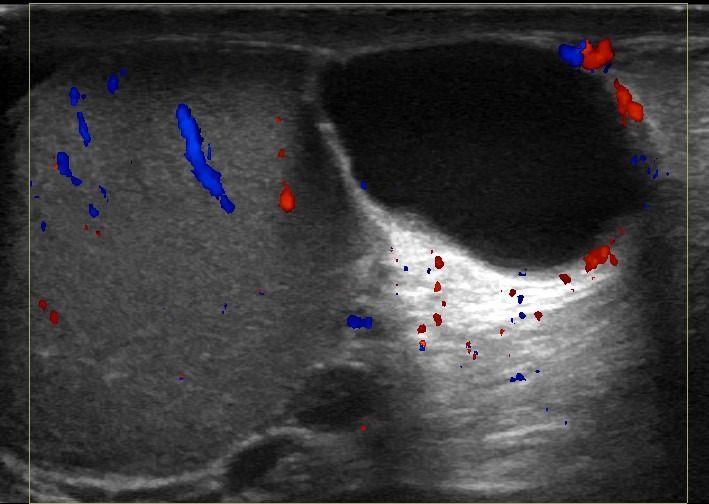

Η μελέτη με Έγχρωμο Doppler παρέχει κρίσιμες πληροφορίες σχετικά με την αγγείωση των όρχεων, ανιχνεύοντας αποκλεισμούς συστροφής ή φλεγμονές, όπως η ορχίτιδα.

- Υδροκήλη